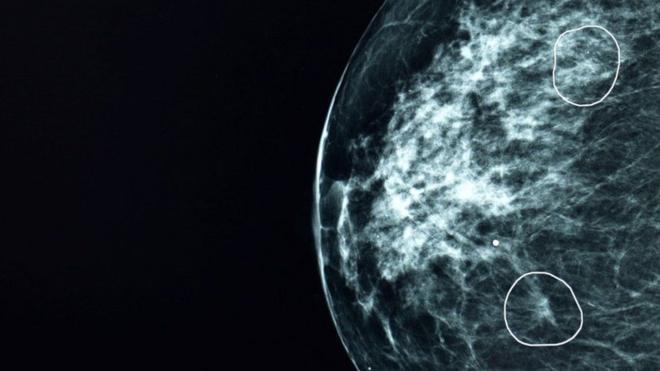

پروفسور اسکویلر سال گذشته اولین بیمار مبتلا به سرطان مغز شد که پیش از خارج کردن غده، با دارو تحت ایمنی درمانی قرار گرفت.

او همچنین اولین کسی است که واکسنی را دریافت میکند که منحصرا بر اساس ویژگیهای تومور او ساخته شده است. این واکسن قدرت داروها برای یافتن سلولهای سرطانی را تقویت میکند.